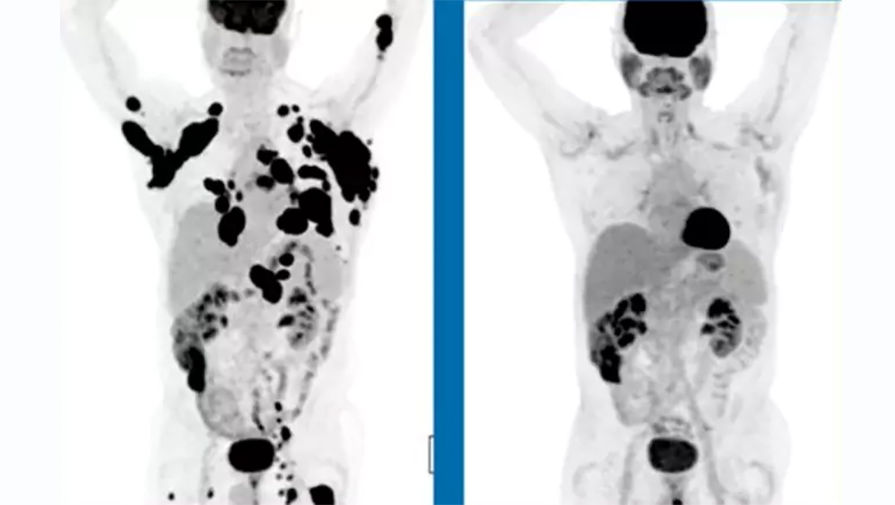

62-летний человек с диагностированной неходжкинской лимфомой в декабре 2015 года и спустя 3 месяца после приема препарата

В исследовании принимал участие 101 пациент с тремя различными формами лимфом, причем в тяжелой, терминальной стадии заболевания, когда никакие способы лечения уже не действовали. В отчете говорится, что у трети таких пациентов спустя шесть месяцев наблюдалась полная ремиссия —

это означает, что спустя полгода в их организме исчезли все признаки заболевания.

При этом у восьми из 10 пациентов опухоли за указанный период сократились как минимум вдвое. «Эти результаты выдающиеся и показывают, что более чем треть пациентов с агрессивной формой неходжкинской лимфомы потенциально могут быть излечимы после одного принятия препарата», — говорится в сообщении компании.